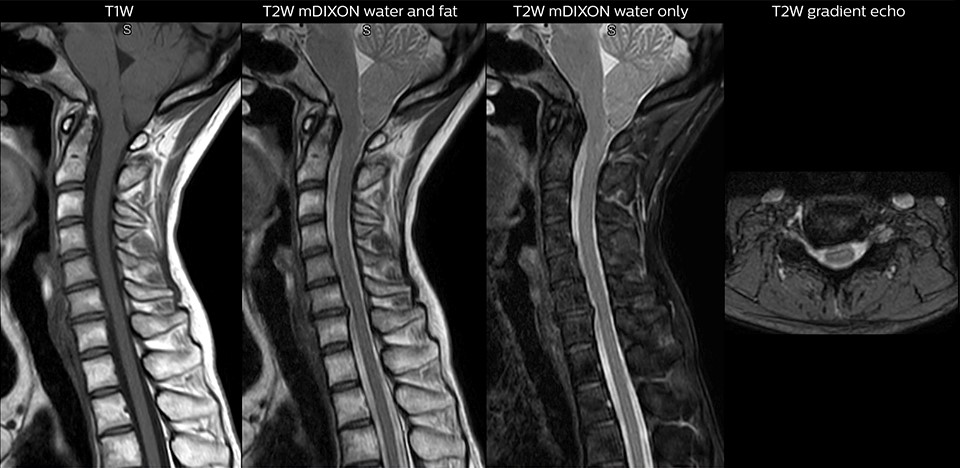

Through Philips mDIXON XD fat suppression application, we can help radiology teams achieve robust capturing of fat-free MRI images in a hectic ED environment. This technology brings a new dimension to fat-free imaging suppression by providing uniform, complete and consistent fat-free images as well as images with both water and fat at the same time, especially useful when time is of the essence Robust with regard to susceptibility-type problems that come up with traditional spectral fat-free images, mDIXON XD can bring speed and clarity to MRI imaging.

High lipid concentration of adipose tissues can make it difficult to interpret MRI exams. Information can be missed when the right acquisitions, such as with as well as without fat suppression, are not included. While this can be solved by adding sequences, this adds to the duration of the exam and increases the likelihood for patient motion – a source of image degradation.